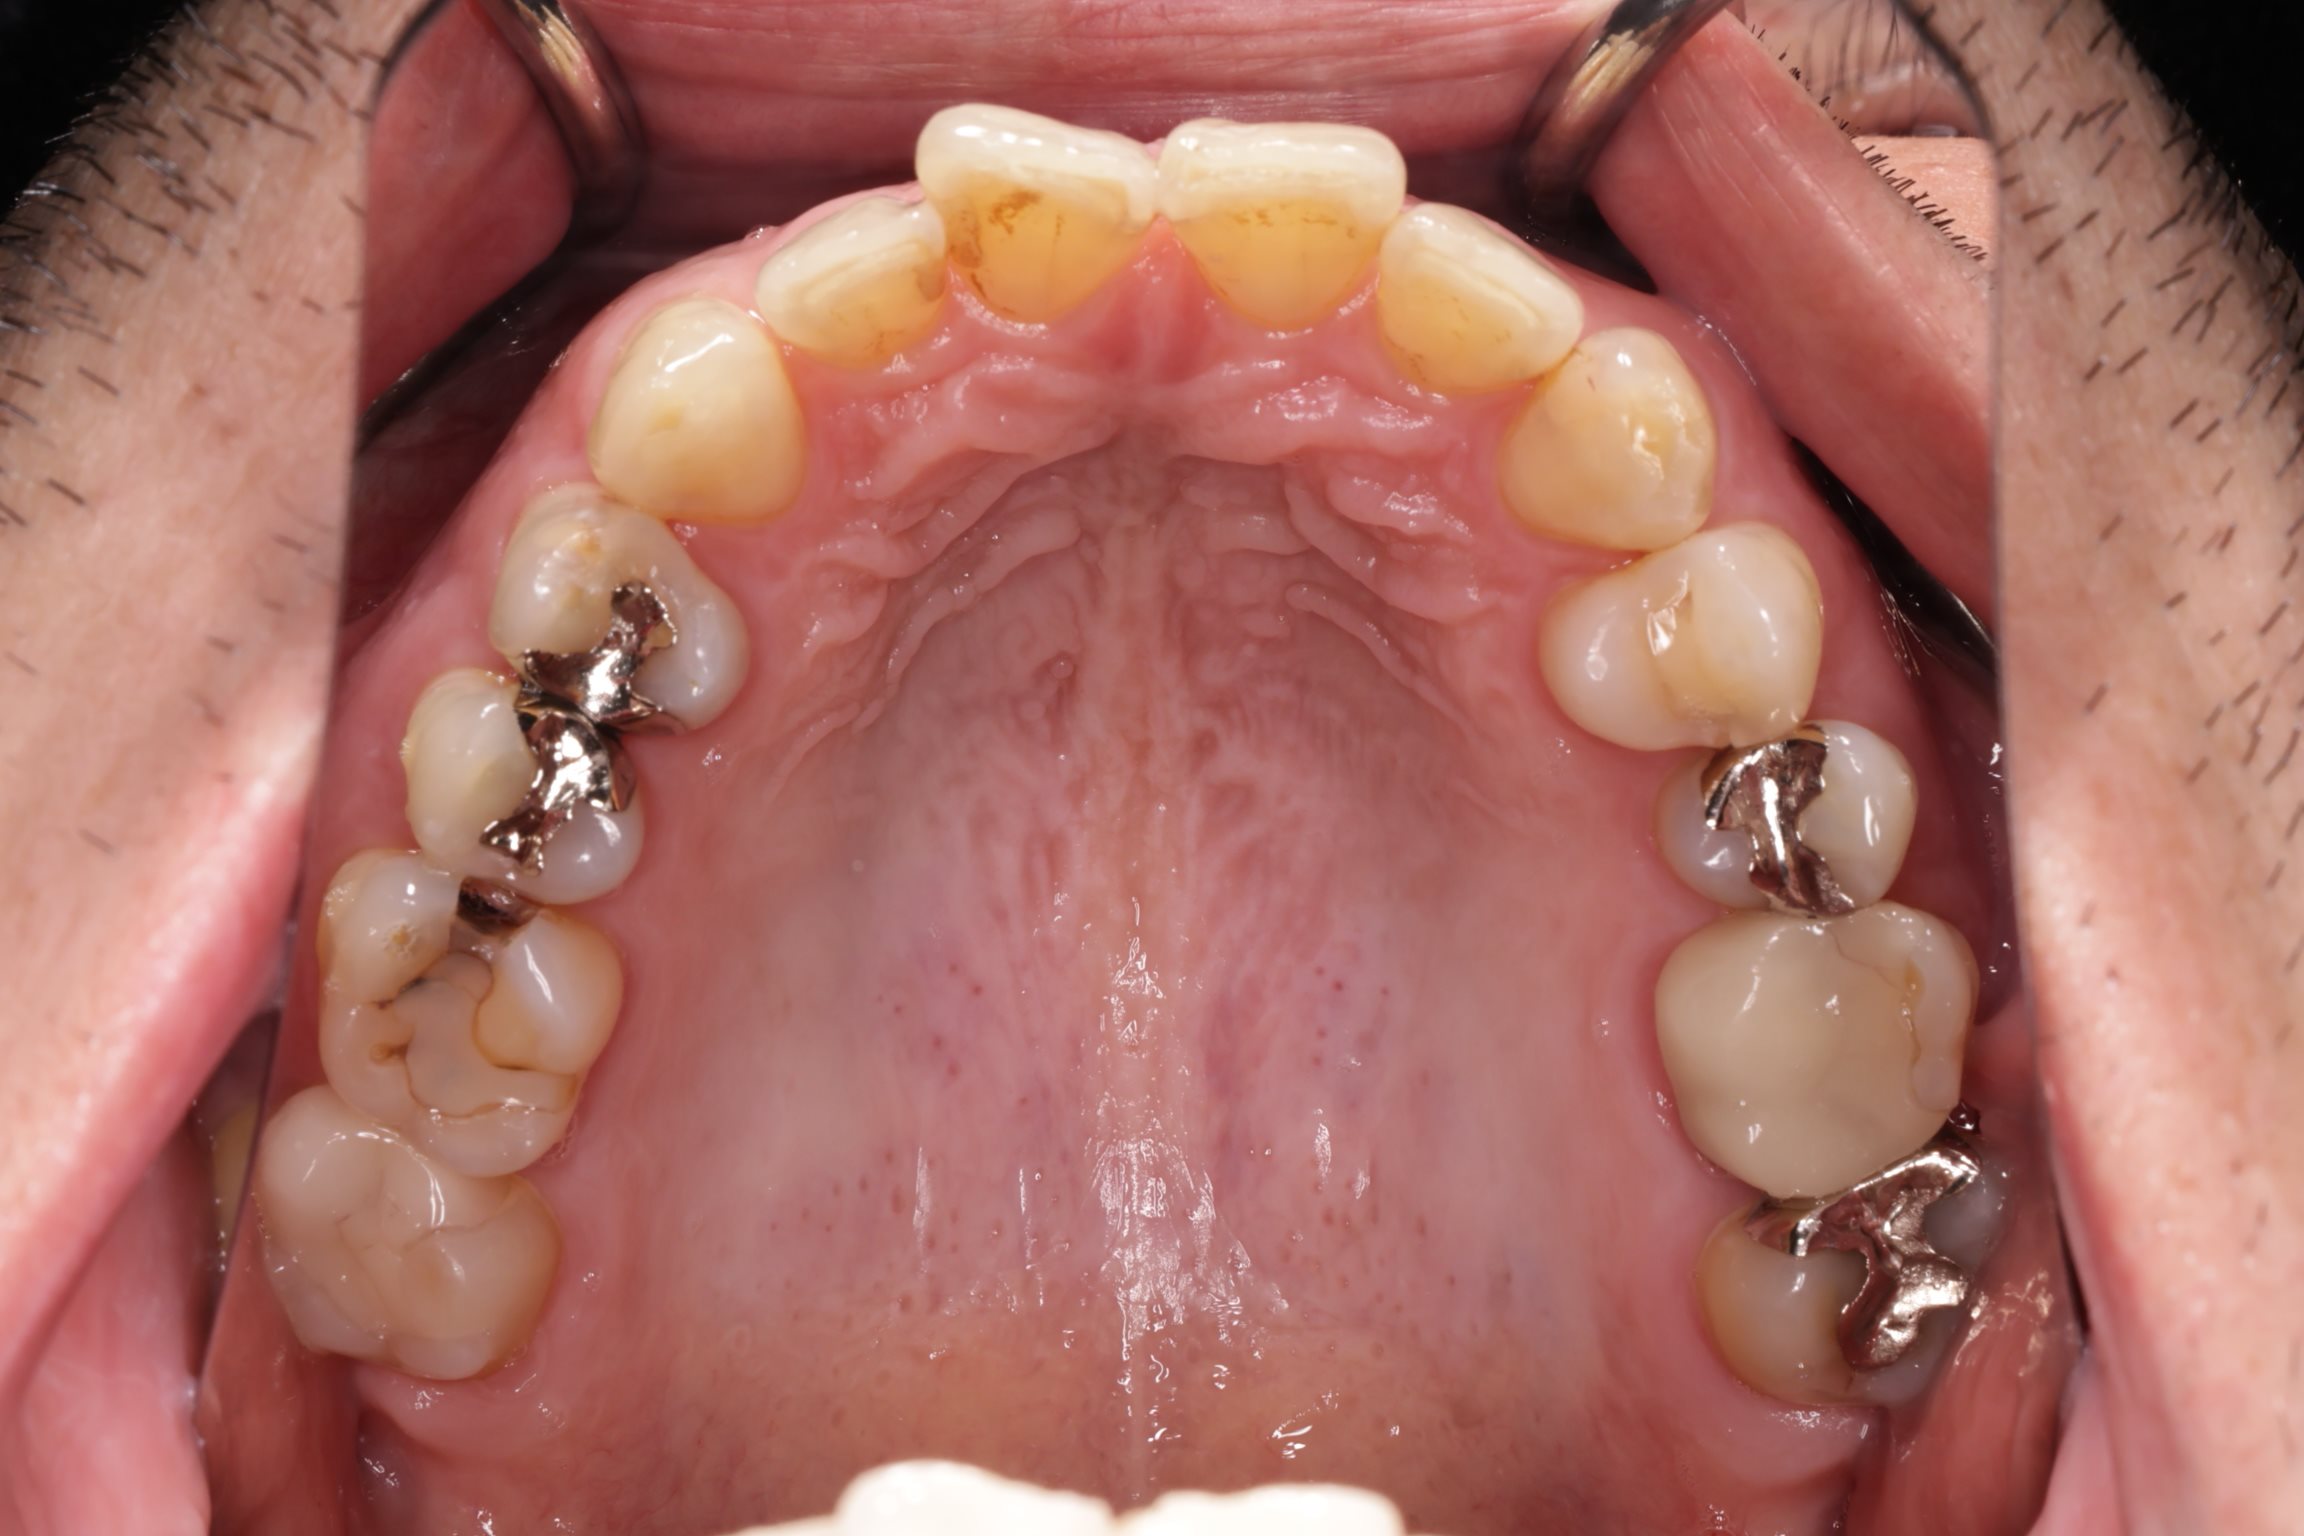

初診時の口腔内の状態:

口腔内には多数の銀歯(銀合金)が確認されました。患者様は過去に多くの虫歯治療を受けており、そのほとんどが保険適用内の銀合金で修復されていました。

患者様はパッチテストによりニッケルなどに対するアレルギーを持っていることが確認されており、口腔内の銀合金もアレルギーの原因となっている可能性が高いと診断しました。また、レントゲン画像を確認すると、被せ物や詰め物の内部、あるいは隙間から、虫歯(カリエス)や根の細菌感染が疑われる状態も確認されました。

Before